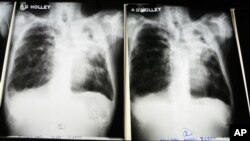

Tuberculosis is one of the world's leading killers. An estimated two-billion people carry the bacterial respiratory infection; more than nine-million people, many living in poverty, have an active form of the disease, which can be spread easily from person to person through the air, by coughing, and by poor sanitary conditions.

Of the nine-million active cases of TB, about half a million are caused by multi-drug resistant tuberculosis, which manifests when the disease pathogen Mycobacterium tuberculosis becomes resistant to isonazid and rifampin, the two drugs most widely used to treat TB.